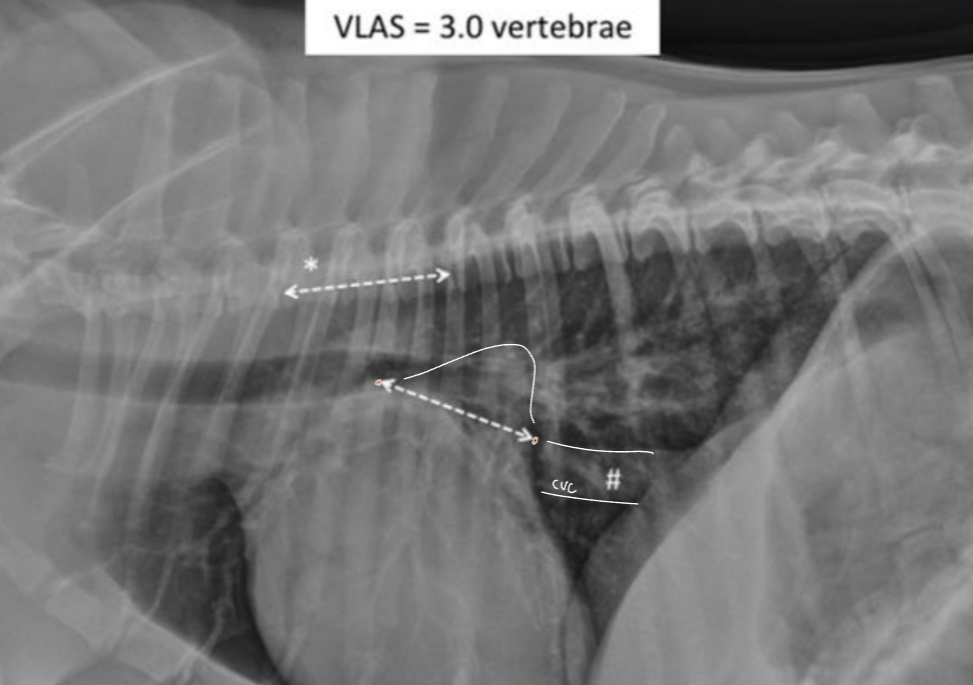

| VLAS | Vertebral left arterial size![]() | ์ข์ฌ๋ฐฉ์ด ์ผ๋ง๋ ์ปค์ก๋์ง ํ๋จ ์ํด ๋์

๋ ์งํ. carina์ 6์ ๋ฐฉํฅ (ventral aspect) ๋ถํฐ CVC์ dorsal border ๊น์ง ๊ธธ์ด๋ฅผ ์ธก์ โ T4 ๋งจ ์์ชฝ๋ถํฐ ๋ค๋ก ๋ช ๊ฐ์ ์ฒ์ถ๋ผ๊น์ง ํด๋น๋๋์ง ํ์ธ. VLAS > 2.3v โ ์ด ์ด์์ด๋ฉด LA enlargement |